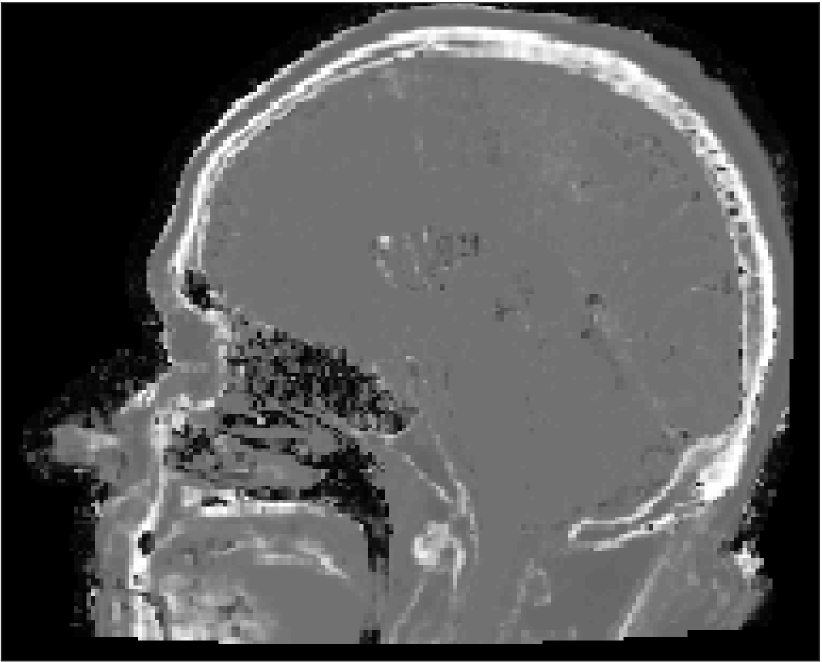

All MR images were acquired with a 1.5 T Siemens Espree scanner. The UTE images were reconstructed to 192×192×192192192192192\times 192\times 192 voxel bitmapped images with an isotropic resolution and a voxel size of 1.33 mm. The UTE sequences sampled the k-space radially with 30 000 radial spokes. CT images were acquired with a tube voltage of between 120 kV and 130 kV on either a GE Lightspeed Plus, Siemens Emotion 6 or GE Discovery 690. The in-plane pixel size varied between 0.48 mm to 1.36 mm and the slice thickness between 2.5 mm and 3.75 mm. Images of the same patient were co-registered and resampled to achieve voxel-wise correspondence between all five modes. A binary mask excluding most of the air surrounding the head was computed from the images and used to remove unnecessary data. Furthermore, to reduce the execution time of the parameter estimation phase, only 11 slices in the middle of the head of each patient was used during the parameter estimation phase, but all slices were used during the prediction phase (s-CT generation). Additional details concerning the data can be found in Johansson et al. [16]. Data from one slice of a patient is shown in Figure 3.

Refer to caption

(a) Binary mask

(b) CT

(c) First echo, 10superscript1010^{\circ}

(d) Second echo, 10superscript1010^{\circ}

(e) First echo, 30superscript3030^{\circ}

(f) Second echo, 30superscript3030^{\circ}

Figure 3: Binary data mask (panel a), CT image (panel b), The four MRI UTE sequences (panels c-f).